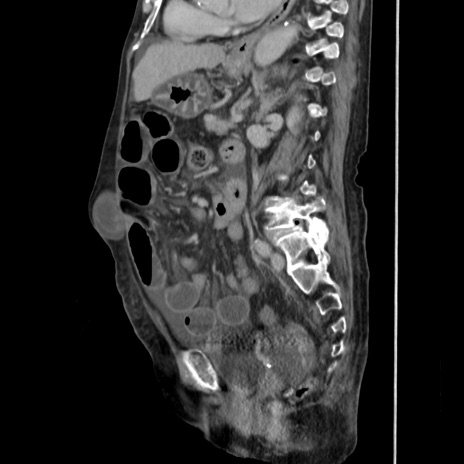

症例31(矢状断像)

【症例】80歳代 女性

【主訴】腹部膨満感

【現病歴】他院にて肝硬変にてフォロー中。1週間前から便秘、腹部膨満感、臍部腫瘤あり受診となる。

【既往歴】肝硬変

【身体所見】腹部膨隆あり、皮膚変化なし、疼痛なし。

【データ】WBC 4600、CRP 0.25